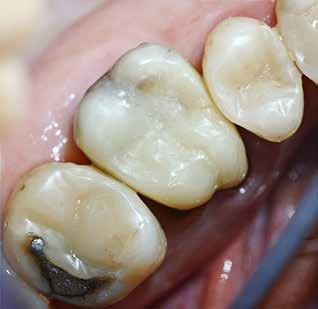

Okklusalt billede af A) over- og B) underkæbe

2. Klinisk ses tydelig slitage ind i dentinen på samtlige tænder fra 6’er til 6’er i begge kæber.

Fig. 2. Clinically, extensive wear into the dentin of all teeth in both jaws is observed.

Klinisk undersøgelse viste et tandsæt med enkelte restaureringer, men med slitagedefekter okklusalt/incisalt på samtlige tænder fra 6’er til 6’er i over- og underkæbe (Fig. 2). Defekterne strakte sig tydeligt ind i dentinen. Baseret på anamnesen og de kliniske fund blev erosion set som hovedårsagen til tandsliddet, mens attrition formodedes at være en medvirkende faktor.